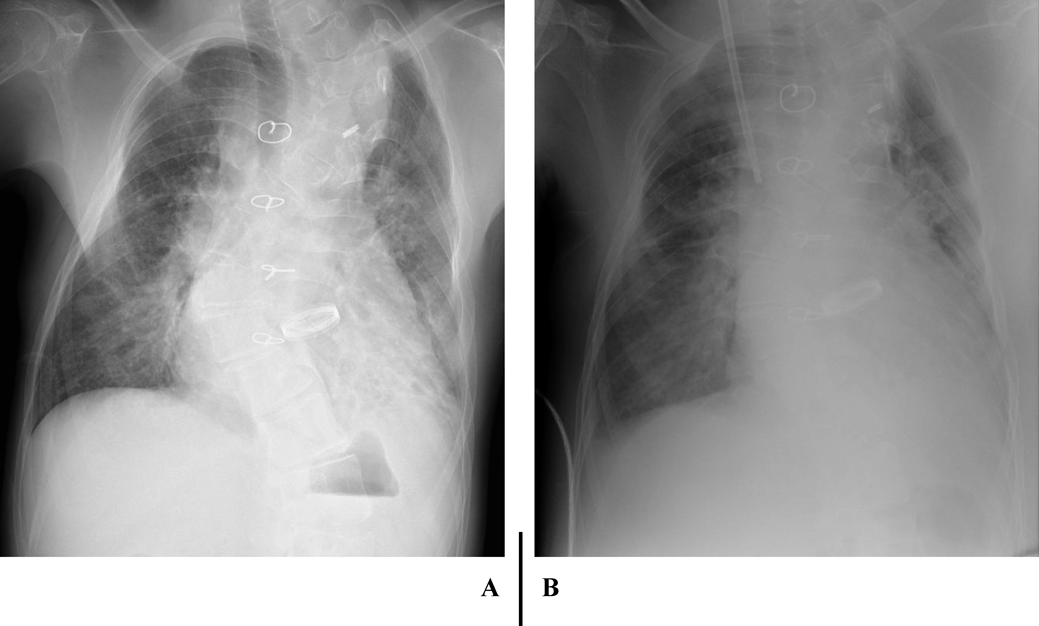

心臓カテーテル検査前日の血液検査(Table 1)で,BUN 40 mg/dL, SCr 0.79 mg/dL, SCrから推定した糸球体濾過量(eGFRcreat) 69.9 mL/min/1.73 m2と,軽度の腎機能低下を認めた.随時尿で150 mg/gCrの微量アルブミン尿を認め,潜血は陰性だった.同日の胸部X線(Fig. 1A)では,心胸郭比63.3%と定期外来受診時と同程度の心拡大および肺うっ血所見であった.入院22日目の心エコー検査では,下大静脈径14.9 mmと拡大し,呼吸性変動は乏しかった(Fig. 2A).両心房の拡大を認め(Fig. 2B),心房間交通は8.9 mmと狭小で右左短絡であった(Fig. 2C).右BTシャント血流は明瞭に描出できたが(Fig. 2D),左BTシャント血流は描出できなかった.

Pediatric Cardiology and Cardiac Surgery 36(2): 166-172 (2020)

Fig. 1 Plain radiograph of the chest shows exacerbation of cardiomegaly (CTR 63→65%), lung congestion, and bilateral pleural effusion, before cardiac catheterization (A) and after initiation of continuous hemodiafiltration (B)

CHDF導入時の胸部X線(Fig. 1B)では,心胸郭比67.7%と心拡大および肺うっ血の増強と両側胸水を認めた.CHDF開始直後に血圧低下,嘔気が出現したため,CHDFを一時中断した.しかし,その後も症状の改善がないためいったん回路を離脱した.CHDF離脱後の心エコーでは,下大静脈の虚脱と左心室の過収縮を認め,脱血による血管内容量の不足を疑い,補液の増量とmilrinoneの減量を行った.プライミングを生理食塩液から赤血球液に変更し,抗凝固薬をnafamostat mesilateからheparin sodiumに変更した上でCHDFを再導入したところ,症状の再燃を認めなかったため除水を開始した.その後も血圧は安定していたため,補液を減量しmilrinoneを再増量した.徐々に呼吸困難が出現し,両側肺野で湿性ラ音を聴取したため,肺うっ血の増強を疑い除水速度を上げて対応した.また,血管透過性の亢進や低アルブミン血症の影響を考慮し,prednisolone 2 mg/kg/dayと25% albuminの投与を行った.CHDF導入2日目には顔面の浮腫や呼吸困難は改善し,血液ガスでpH 7.334, HCO3 −19.4 mmol/L, BE −5.8 mEq/Lと代謝性アシドーシスの改善を認めた.脱水傾向で除水速度を下げたが,その後徐々に血圧が上昇し,収縮期血圧200 mmHgと高血圧を認めた.除水速度を上げmilrinoneを増量したが改善しないため,nicardipine hydrochlorideの投与を開始したところ,血圧は正常域に改善した.CHDF導入4日目にはSCr 0.97 mg/dLまで低下したものの,尿量は増加傾向なく胸水の再貯留を認めたため,輸液を減量し,除水速度を上げて対応した.CHDF導入6日目から利尿薬の投与に反応を認めるようになったため,導入7日目にCHDFを一時中止した.その後もSCrの上昇や代謝性アシドーシスの再燃なく,自尿で3,100 mL/dayと十分量保たれていたため,導入8日目にCHDFを離脱した.離脱後も腎機能の増悪や乏尿の再燃はなく,CHDFの再導入を必要としなかった.退院時の腎機能および尿所見は入院前と同程度に改善していた(Table 1).